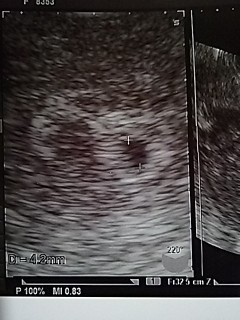

長い間不妊治療をしてきてようやく授かった命。 実は2ヶ月前に体外授精後、妊娠8週目で完全流産してしまい、辛かったけどここまで諦めないで頑張ってきて良かった。 つい先日、鮮血と下腹部痛に見舞われたけど止血剤と痙攣を止める薬を処方してもらい、なんとか無事。 赤ちゃん、このまま無事に元気に産まれてきてね。 4.2㎜でした。